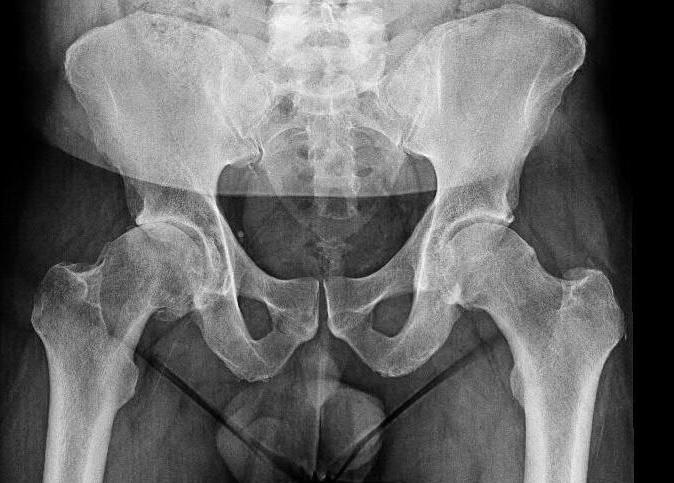

Si bien, la cuasa más freuccente de indicación de reemplazo de cadera es al artrosis, ya sea primaria o secundaria o cuadros como la displasia de cadera, la osteonecrosis, enferemdades articulares inflamatorias... también peude ser necesario la colocación de una prótesis de cadera en pacientes con algunos tipos de fractura de cadera.

- Artrosis de cadera: por el desgaste del cartílago que recubre la superficie de la cabeza femoral y o de la cetábulo, lo cual puede deberse al sobreuso debdo a causas desconocidas o patologías previas que aceleren su desgaste.

A continuación os mostramos el antes y el después de un caso clínico tratado por nuestro equipo de traumátologos.